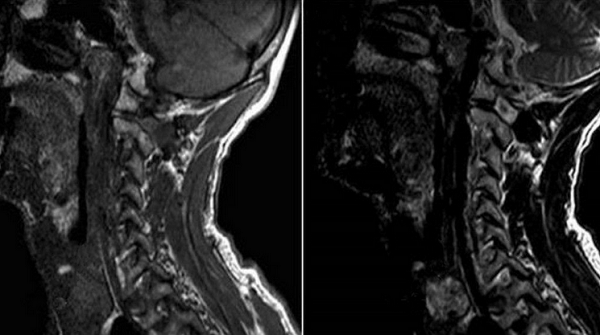

Снимки МРТ мягких тканей шеи

Рисунок 1,2. МРТ мягких тканей шеи (Т2-ВИ и Т1-fs-ВИ контрастное усиление). Патологических образований в структуры щитовидной железы не выявлено.